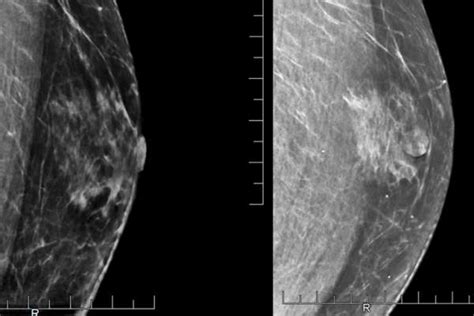

Research suggests that pregnancy and breastfeeding, however, lower a woman's risk of breast cancer. Women who have been treated for breast cancer with partial or total mastectomy may have reduced capability to breastfeed or produce breast milk. Instead, you may notice a rash that looks like an insect bite. Breastfeeding at diagnosis because cancer is difficult to detect in a lactating breast, it is unusual—though not impossible—for women to be diagnosed during the time they are breastfeeding. If you can and want to breastfeed, definitely do it, especially if someone in your family, like your mom or sister, has had breast cancer.

For most of us, drinking is social. After breast cancer, some women also find that breastfeeding helps them regain good feelings about their bodies. It also can lower your breast cancer risk. Breast infections are common while breastfeeding. After breastfeeding, when the tissue is softer, clogged milk ducts and any other growths in the breast tissue should be expected to feel more noticeable as the surrounding breast tissue is. Breastfeeding also lowers a mother's risk of high blood pressure, type 2 diabetes, and breast and ovarian cancers. Swelling or lumps around your collarbone or armpits can be caused by breast cancer that has spread to lymph nodes in those areas. If you have breast cancer while lactating, you may need surgery, chemotherapy, or radiation. Breastfeeding at diagnosis because cancer is difficult to detect in a lactating breast, it is unusual—though not impossible—for women to be diagnosed during the time they are breastfeeding. Breastfeeding is one of the first (and most personal) decisions a mother makes for her baby. Women who have been treated for breast cancer with partial or total mastectomy may have reduced capability to breastfeed or produce breast milk. When breastfeeding is going well and if you don't plan on being parted from your baby, a breast pump is not an essential purchase. If you have breast cancer, the doctor will want to find out how far it has spread.